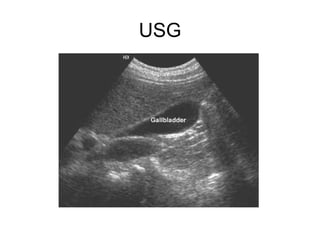

USG